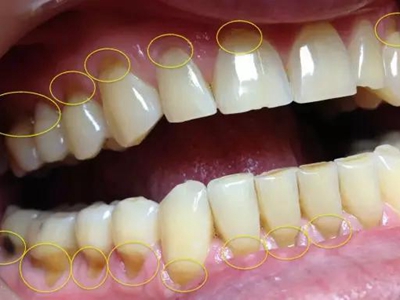

楔状缺损与年龄相关,即年龄越大,缺损越重,患者多有横刷牙习惯,患牙为多颗甚至全口,常以口角附近的牙齿(尖牙、前磨牙)为重。典型表现为牙颈部缺损,呈楔形,由两个夹面组成,口大底小,缺损处质地坚硬,表面光滑,边缘整齐,无染色,轻微泛黄常为牙齿本色,严重时可导致牙髓腔暴露甚至牙齿横向折断,根据缺损深浅不同,可伴有牙齿敏感甚至疼痛。

不正确的刷牙方法,尤其是横刷法是发生楔状缺损的主要原因,因为牙颈部结构比较薄弱,易发生磨损。另外,颊面牙颈部是咬合应力集中区,长期的咀嚼压力使牙体组织疲劳,应力集中区出现破坏,也会造成楔状缺损。龈沟内酸性渗出物,也与楔状缺损的发生有关。